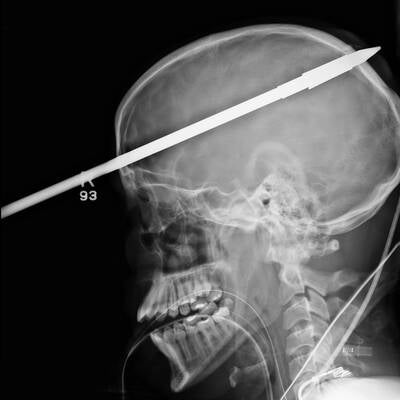

Es ist ein Wunder: Eine zwei Meter lange Eisenstange durchbohrte den Kopf von Eduardo Leite (24) aus Brasilien – und der Bauarbeiter hat es überlebt!

Ein wahres Wunder hat sich in Rio de Janeiro (Brasilien) ereignet: Eine Eisenstange stürzte aus gut 5 Metern Höhe auf den 24-jährigen Bauarbeiter Eduardo Leite. Ein Aufschrei bei seinen Kollegen, als sich die Stange durch seinen Helm hindurch in den Kopf bohrt und zwischen den Augen wieder heraustritt – ein Bild des Horrors!

In einer Notoperation kämpften die Ärzte um das Leben von Eduardo Leite. Sie öffneten den Schädel und entschieden sich, die Stange aus der gleichen Richtung zu entfernen, aus der sie in den Kopf eingedrungen war.

Nach fünf Stunden hatten die Ärzte das Leben des Mannes gerettet – Folgeschäden dürfte er nur in geringer Form durchleiden müssen. „Es war wirklich ein Wunder“, so der betreuende Arzt Luiz Essinger.